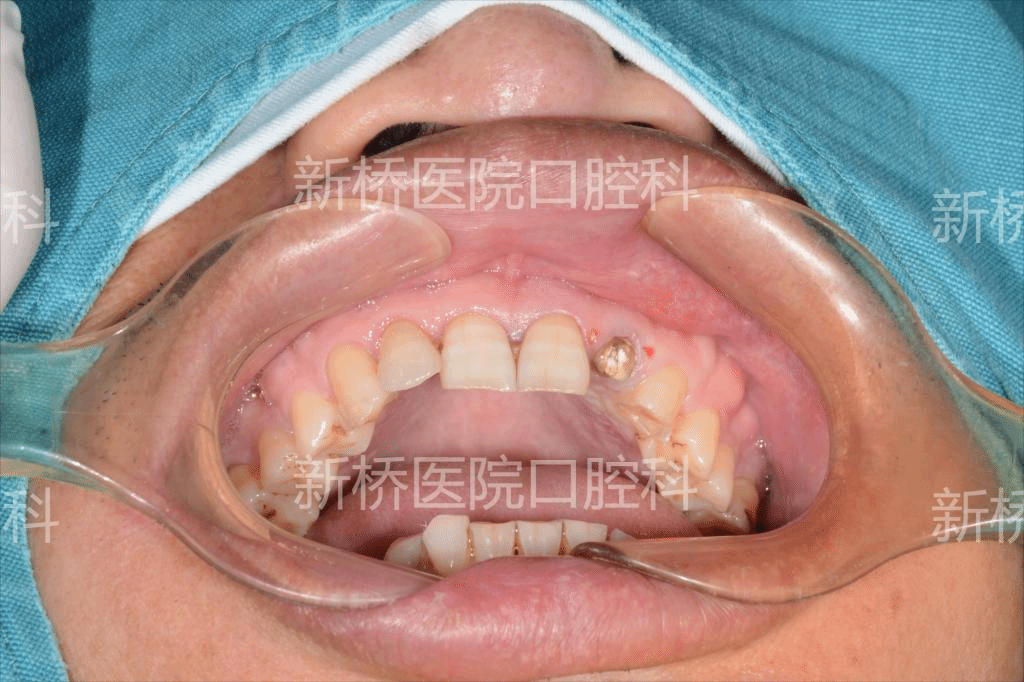

②:自体牙移植术是一种将患者自身健康的牙齿从一个位置移植到缺失牙或需要拔除患牙的位置的手术方法。常见的供体牙包括智齿、埋伏牙、错位牙或异位萌出牙等无功能牙。该手术可以实现“变废为宝”,用患者天然无功能牙牙恢复其缺失牙,维持牙槽骨的骨量,并保留牙周组织的正常功能。是一种高效、经济且生物相容性极佳的牙齿修复方法,尤其适合有理想供体牙的年轻患者。